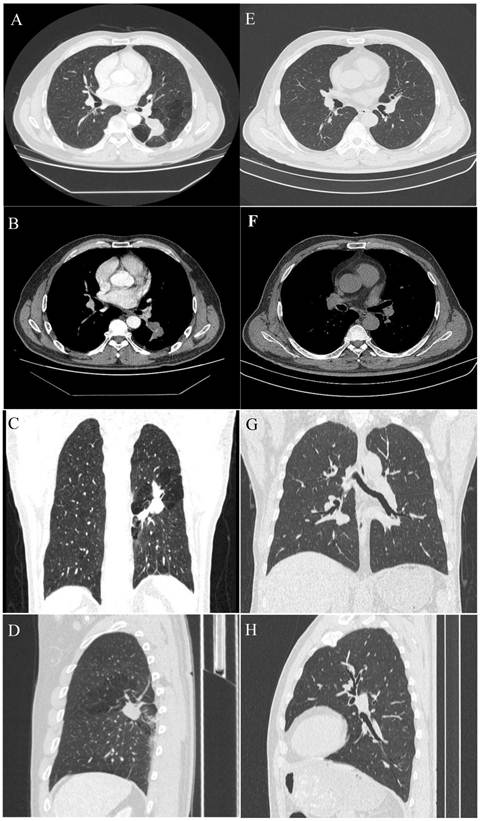

The collected imaging results are shown in Fig. 1.

Figure 1

A 54-year-old male with a pulmonary lesion identified on a routing chest computed tomographic scan. Axial lung window (A), axial soft-tissue window (B), and minimum-intensity-projection (MinIP) lung window coronal (C), and sagittal (D) contrast-enhanced CT images show a dilated, club-like structure surrounded by emphysematous changes of the peripheral lung fields at the superior segment of the left lower lobe; computerized tomography number is 28 HU; non-enhancement of the structure is shown on contrast-enhanced CT. The orifice of the superior segmental bronchus was not observed. CT features indicate a diagnosis of bronchial atresia. E, F, G, H are the corresponding normal control CT findings of A.B, C, D.

On chest radiographs, ten patients had hilar mass-like shadows, and two had pneumonia-like shadows. Most (n = 8) showed hyperlucency of the peripheral lung fields. CT revealed a mucocele in all patients (n = 12); the mucoceles were round in 4 patients and club-like in 8. In 80% of the cases (n = 10), associated anomalies, including occlusions of the bronchus central to the mucocele, emphysematous changes of the peripheral lung fields, bronchogenic cyst, and anomalous branchingof bronchial tree and vascular structure. In some cases, post-processing of CT data was conducted using 3D reconstruction, which clearly revealed the hyperinflation and a dilated bronchocele. In our study, CBA was involved the right lobe in 8 patients and the left lobe in the remaining 4.